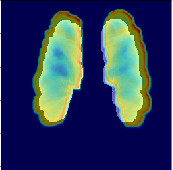

Refer to caption

(a) Input

(b) Feature 1

(c) Feature 2

(d) Heatmap

Figure 5: Image with extracted features

Recent attempts to demystify the neural network black box have included the Grad-CAM [24] project, which introduced a technique to visualize the weights of a layer that most strongly correlate with the final decision. It attempts to maximize the outputs of that particular layer with respect to a desired filter (class). This technique was used to generate the heatmaps representing sources of influence to the prediction shown in figure 1 and figure 5(d), where the selected layer was the final fully connected layer in the graph from the most recent convolution layer and the filter was for images which were predicted to be in the cancerous class. It is important to note that it is impossible to verify whether the heatmap activations correspond to the actual location of the malignant nodules or masses given the binary dataset. Coincidentally, the PLCO dataset provided radiologist annotations detailing a variety of lung abnormalities and their locations. One such abnormality was the presence of nodule masses. The heatmap markings seen in Figure 1 correspond directly to the nodule masses noted location by a radiologist. However, it is important to clarify that a nodule mass does not always lead to lung cancer, but it is an interesting correlation.